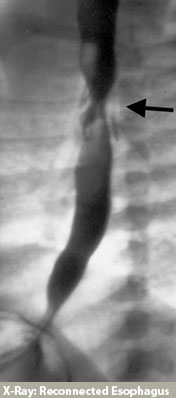

At the time of esophageal repair, a tube will be placed in your child's chest to drain any fluid that might accumulate near the surgical site. Several days after surgery a special x-ray, called a contrast esophagram, will be performed. This test is done to ensure there are no leaks along the esophageal repair. If the incision has healed, without a leak, the chest tube will be removed and feedings will be started by mouth. In some cases the esophageal repair may take longer to heal, and a leak will be visible on the x-ray study. If there is a leak, the chest tube will remain in place until the leaking stops. X-ray studies will be repeated every several days until the esophageal repair has completely healed.

When do I see the surgeon after the hospital discharge?

If all is going well, a visit to our office at a specific time is not required. A visit to your child's Primary Provider, at one to two weeks after the discharge, is recommended. Children with esophageal atresia and tracheoesophageal fistula may develop esophageal narrowing (stricture) at the site of repair. If this occurs, your child will have trouble swallowing liquids or solids. If the problem is severe you may notice your child coughing or choking on food, vomiting, or refusing to take food or liquids. If you suspect there is a stricture call our office as soon as possible. We will arrange for a special x-ray called an esophagram, which will help identify any narrowing or stricture of the esophagus. Surgical dilation (stretching) of the esophageal stricture may be required and will be performed under anesthesia.